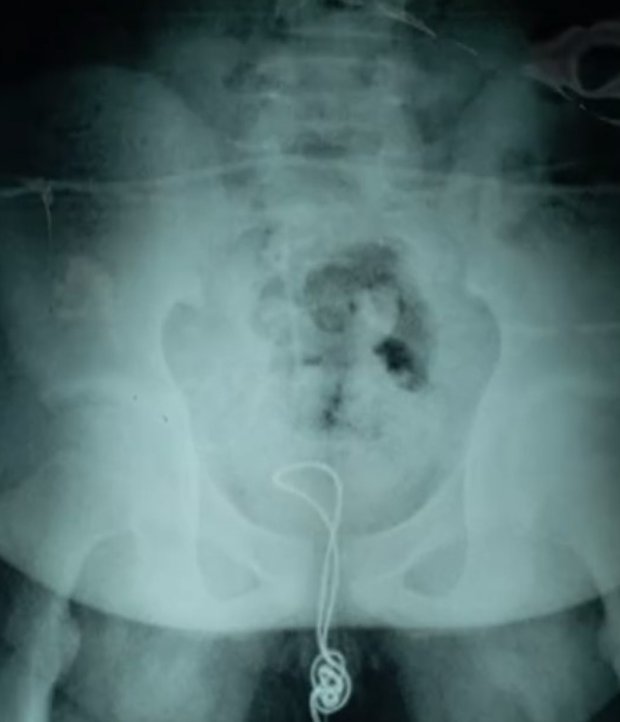

Ο 13χρονος, εξερευνώντας τον εαυτό του, αποφάσισε να δοκιμάσει να βάλει ένα καλώδιο USB στο πέος του, αφού πρώτα έκοψε την μία άκρη το βύσμα.

Μάλιστα κατάφερε να το εισχωρήσει περίπου 20 πόντους, με αποτέλεσμα να φτάσει στην κύστη και να μην μπορεί να το βγάλει.

«Έκοψε την μία άκρη του καλωδίου, την έβαλε στην ουρήθρα του και έφτασε μέχρι την κύστη του.Εκεί μπερδεύτηκε και δημιουργήθηκε κάτι σαν κόμπος, με αποτέλεσμα να μην βγαίνει προς τα έξω και να μείνει κολλημένος», είπε η γιατρός Χου, λίγο μετά την επέμβαση που πραγματοποίησε στην ουροδόχο κύστη.